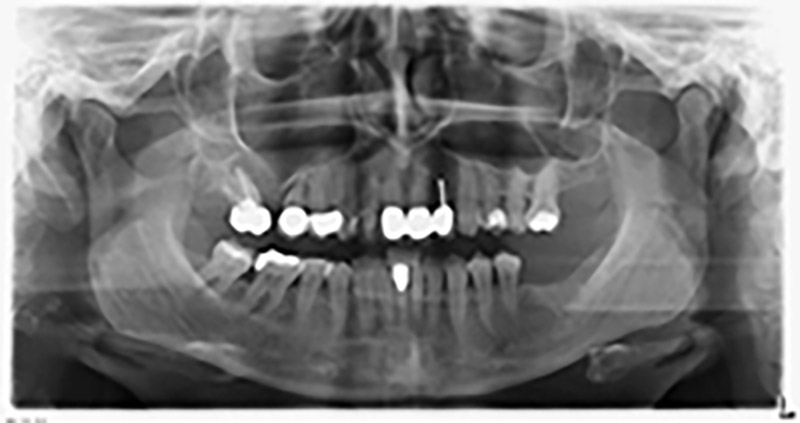

59-годишна пациентка с напреднал стадий на пародонтит описва неприятно чувство и лош вкус в първи квадрант в дисталната зона. Клиничният преглед разкрива силно уголемени пародонтални джобове и напреднала костна атрофия в зона 16 и 14. Рентгенографията потвърждава констатациите (Фиг. 1). Зъби 16 и 14 не могат да бъдат запазени.

Снимка 1: Ортопантомография с костна атрофия в зони 16–14.*